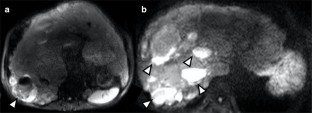

Liver cysts are observed in 83% of cases of autosomal dominant polycystic kidney disease (ADPKD). Although not as prevalent as renal cyst infection, liver cyst infection is a serious complication that is sometimes difficult to treat. We report the case of a maintenance hemodialysis patient with ADPKD who received a living donor liver transplantation alone (LDLTA) due to refractory liver cyst infection. The patient was a 67-year-old Japanese man who developed fever and right-side abdominal pain, and liver cyst infection was suspected. Treatment with multiple antibiotics was ineffective. Many liver cysts were observed on magnetic resonance imaging scans and a cyst in liver segment S6, which produced the strongest signal variation, was drained. The fever subsided temporarily, but multiple infected liver cysts were observed on follow-up imaging examination; 4 months later, hepatectomy and LDLTA were performed. Although LDLTA due to refractory liver cyst infection in maintenance hemodialysis patients with ADPKD is risky and should be carefully considered, it may be the only effective treatment.

Fig. 1